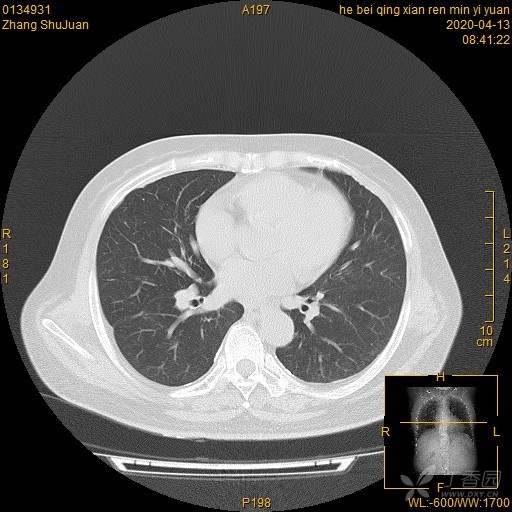

右肺结节猜病理,有结果(得细心,这个很有意思)(俱乐部3)

西门开心 +5 丁当患者性别:女

患者年龄:49

简要病史:体检发现右肺结节,不吸烟。

体格检查:无阳性体征

辅助检查:血常规、血沉正常,血肿瘤标志物正常。FET-CT倾向恶性结节

临床诊断:右肺结节

治疗经过:手术

大家猜猜病理是什么?